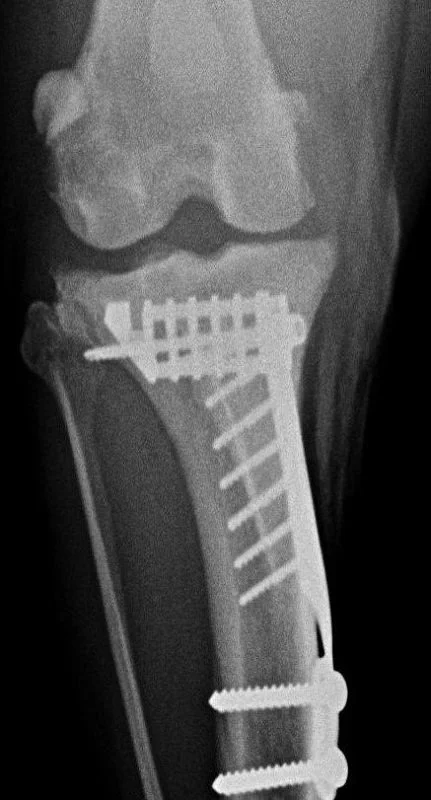

Behandlung von Frakturen

Orthopädisch behandeln wir Frakturen mittels Platten, ­Nägeln und Fixateur externe. In der Gelenkschirurgie behandeln wir Kreuzbandrisse, Kniescheibenluxationen und Arthrodesen. Eingriffe an Schulter und Ellbogen werden wenn möglich arthroskopisch durchgeführt.

im Röntgenbild

Eingriff